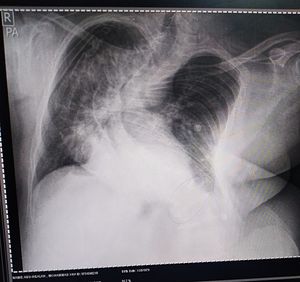

PA CXR

Congenital

Chest

Sclerosis